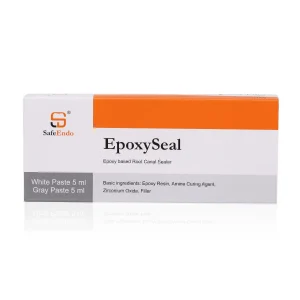

₹1,050 Original price was: ₹1,050.₹794Current price is: ₹794.

Features- Resin-based, non-acrylic, eugenol-free sealer. Excellent radiopacity. Suitable for all obturation techniques. Outstanding dimensional stability and low solubility for a durable, safe seal Excellent flow characteristics to flow into and seal lateral canals Thermoplastic ability makes it easy to remove Description- SafeEndo EpoxySeal is a resin based root canal sealer which is a paste-paste type of dual…